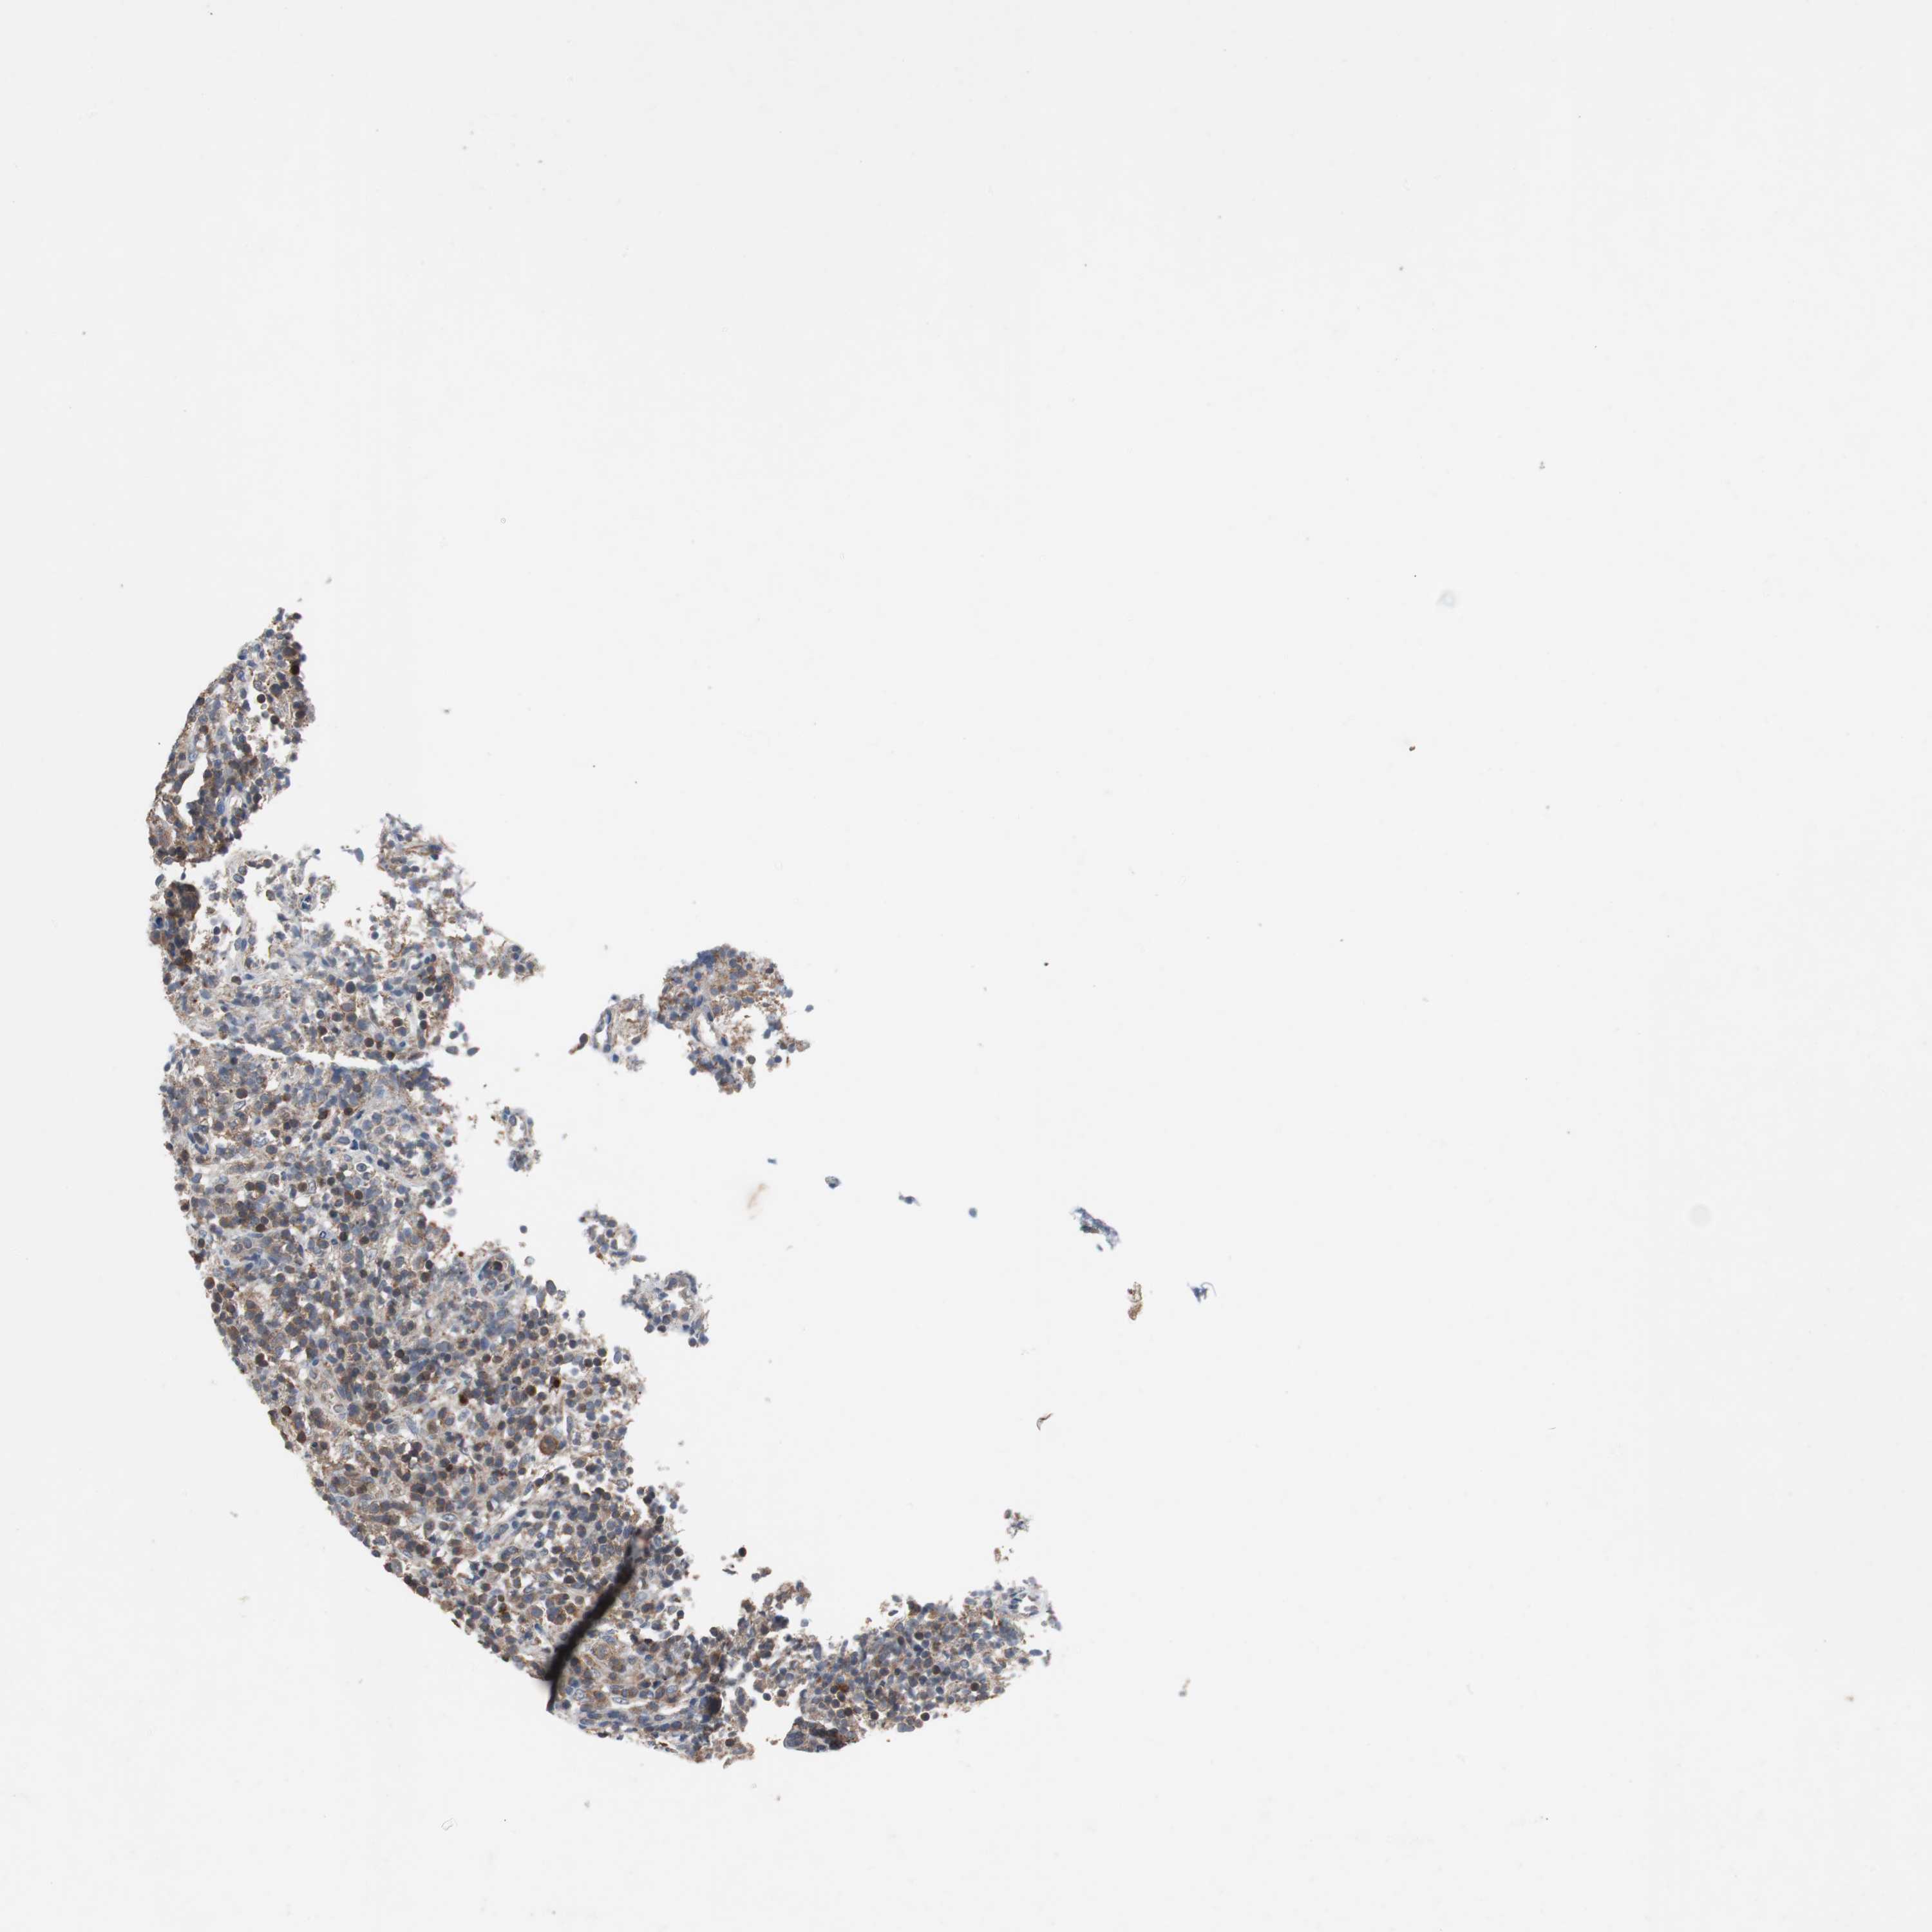

LYMPHOMA - Protein expressioni

A mouse-over function shows sample information and annotation data. Click on an image to view it in a full screen mode. Samples can be filtered based on level of antibody staining by selecting one or several of the following categories: high, medium, low and not detected. The assay and annotation is described here.

Antibody HPA007305

Staining

High

Strong

>75%

Nuclear

Hodgkin's disease, NOS